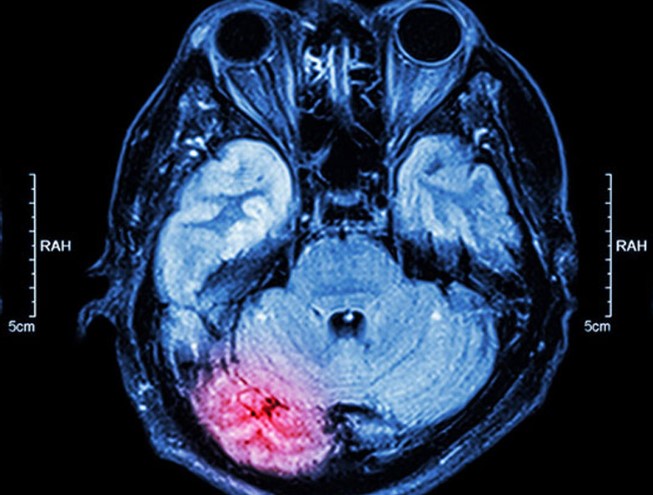

Sağlık fizikçisi nedir? Sağlık fizikçisi ne iş yapar? Bilindiği üzere radyasyon kaynakları sağlığın temelini oluşturan pek çok uygulamalarda aktif olarak kullanılır? Tanı ve tedavi sürecinde kullanılan bu radyasyondan sağlık fizikçileri sorumludur. Sağlık fizikçisi nedir ne yapar kısmında görev tanımı kapsamında sayılabilecek detaylar şu şekildedir;